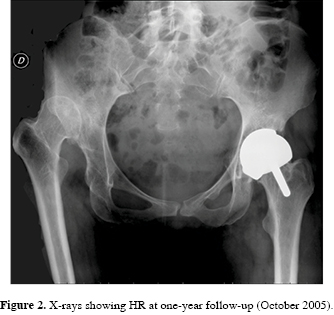

Considering the young age of the patient and the preserved femoral morphology, a HR was performed on the left hip (BHR, Birmingham Hip Resurfacing, Smith & Nephew, Birmingham, United Kingdom) in December 2004 (46-mm cemented femoral head, 52-mm uncemented acetabular cup). The acetabular shell was positioned with an inclination of 67o (Figura 2).

Ten months later, the patient was completely satisfied with her HR, HHS increased to 91. Due to the resurfaced left hip, limb-length discrepancy increased to 57 mm. Considering the positive clinical outcome, the patient wanted to receive the same treatment in the contralateral hip.